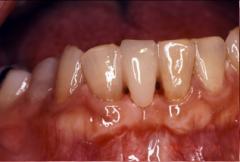

CR接着修復法治療例(2):52歳 男性

抜けた前歯をつくる(直接CR接着ブリッジ法)

治療前

下の前歯が1本抜けてしまっていました。

治療後

両隣の歯に接着処理をおこない、口の中でCR(コンポジットレジン)を築盛して歯を一本作りました